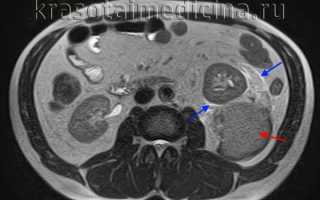

Диагноз устанавливается врачом-урологом, подтверждается на основании клинических признаков, анализа мочи, МРТ, КТ, УЗИ, внутривенной урографии, нефросцинтиграфии и почечной ангиографии. Для оценки тяжести кровопотери осуществляется контроль уровня гемоглобина и гематокрита. При подозрении на сочетанную травму назначаются консультации различных специалистов: травматолога, абдоминального хирурга и пр.

image

МРТ ОБП. Повреждение левой почки. Забрюшинная гематома (красная стрелка), отек перинефральной клетчатки (синяя стрелка).